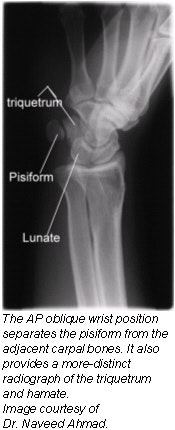

Positioning for AP oblique wrist projection (medial rotation)

- Place the cassette under the wrist and center it at the dorsal surface of the wrist.

- Rotate the wrist medially (intimally) until it forms a semisupinated position of approximately 45° to the cassette.

- CR: Perpendicular to the midcarpal area, it enters the anterior surface of the wrist midway between its medial and lateral borders.

Evaluation criteria

- Carpals on medial side of wrist.

- Triquetrum, hamate, and pisiform free of superimposition and in profile.

- Distal radius and ulna, carpals, and proximal half of metacarpals.

- Soft tissue and bony trabeculation should be visible.